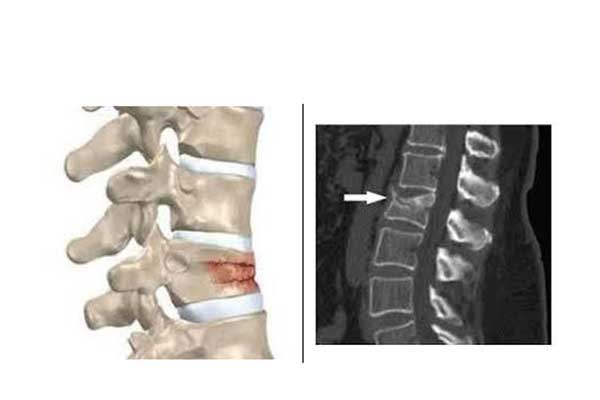

Transdermal kyphoplasty is a minimally invasive procedure for the treatment of vertebral compression fractures, which are fractures of the vertebral bodies that form the spine. When a vertebral body is fractured, the usual rectangular shape of the bone is compressed causing pain. These compression fractures can occur in one or more vertebrae in the spine and are usually a consequence of osteoporosis.

We use X-ray guidance to insert a balloon through a needle into the vertebral fracture, which extends upwards realigning the bone and creating a cavity within the vertebra. The fractured vertebrae are strengthened by the injection of special hardening material into the cavity when the balloon is removed. The surgical incision is about 0.5 cm.